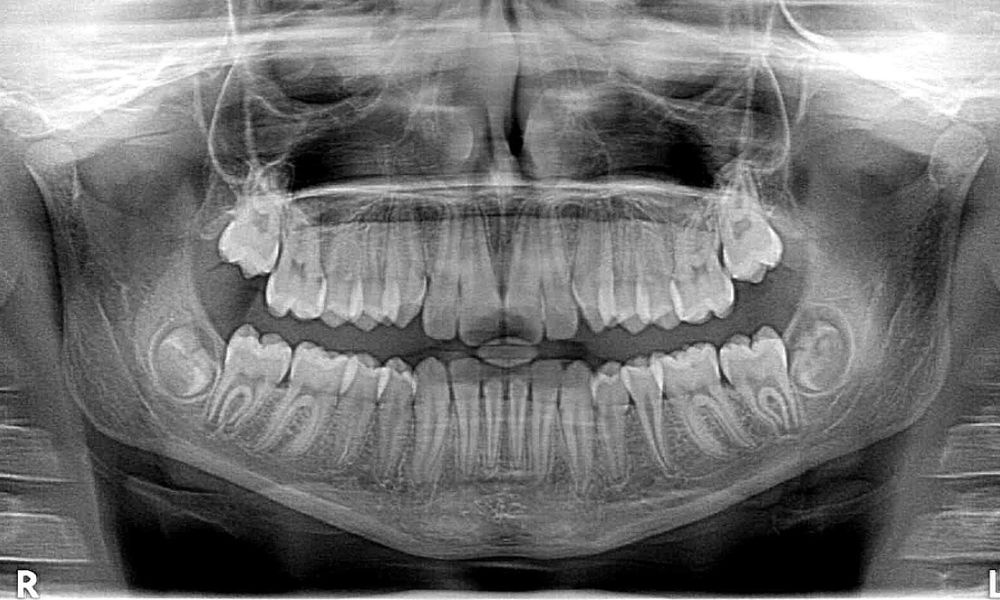

Wie ist unser Gebiss aufgebaut?

Uns stehen in unserem Leben zwei Sätze von natürlichen Zähnen zur Verfügung, die schon vor der Geburt im Kiefer angelegt sind: die Milchzähne und die bleibenden Zähne. Insgesamt vergehen rund zwei Jahrzehnte…